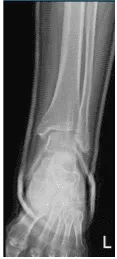

El paciente presentó un resultado de radiografía y el estado tras la aplicación externa de un yeso por fractura oblicua ligeramente desplazada de la fíbula distal.

Radiografía del tobillo izquierdo completa: 3 o más vistas